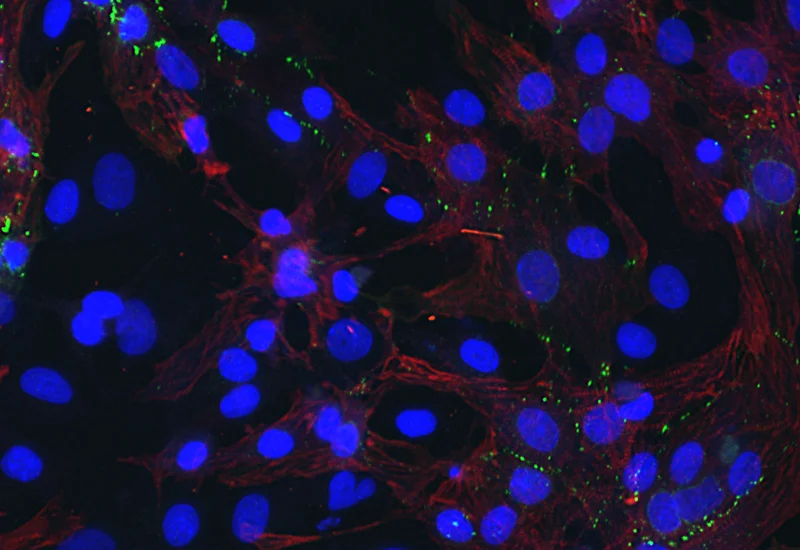

Original Image